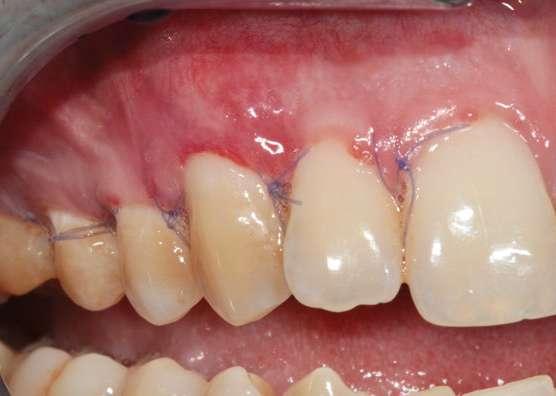

Figura 5. Colgajo elevado “Split-Full-Split” y fijación de los injertos de tejido conectivo con suturas 7/0 reabsorbibles (PGA).

Figura 7. Post-operatorio y excelente curación 7 días después de la cirugía.

Figura 6. Avance coronal sin tensión y sutura del colgajo mediante puntos “sling” con sutura 6/0 reabsorbible (PGA).

La curación fue excelente y los puntos de sutura se retiraron a las 3 semanas post-operatorias (Fig. 7).

Se presentan fotografías clínicas de la evolución y seguimiento a 6 meses, 12 meses y a 5 años (Figs. 8-10). A pesar de una mínima recidiva de menos de 1 mm en la recesión del diente 2.1, es interesante y reconfortante observar la gran estabilidad clínica de los tejidos blandos, así como un color, textura y forma muy armónicos de toda la encía tratada. En gran parte también gracias a un excelente cepillado y mantenimiento periodontal.